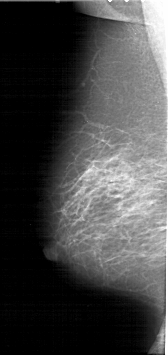

RIGHT_CC LINES 6331 PIXELS_PER_LINE 3046 BITS_PER_PIXEL 12 RESOLUTION 43.5 OVERLAY

FILE: A_1371_1.RIGHT_CC.OVERLAY

TOTAL_ABNORMALITIES 1

ABNORMALITY 1

LESION_TYPE MASS SHAPE LOBULATED MARGINS OBSCURED

ASSESSMENT 4

SUBTLETY 3

PATHOLOGY BENIGN

TOTAL_OUTLINES 1

BOUNDARY